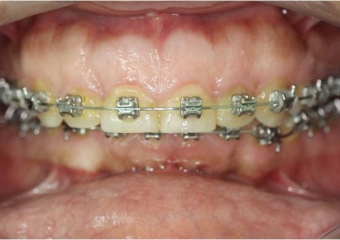

Mordida final